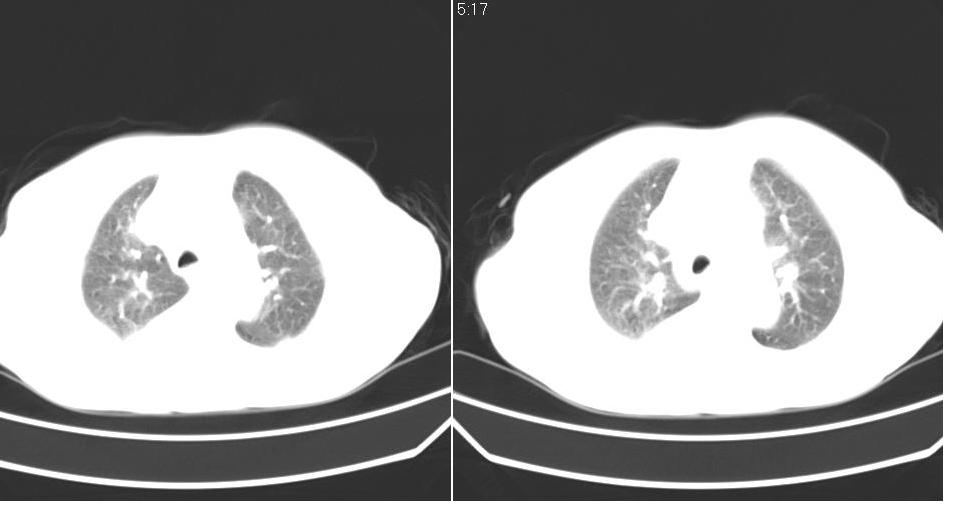

以下是引用liaizhi在2007-7-11 15:41:00的发言:[br]两肺纹理增粗,肺门影增大,气管支气管通畅。升主动脉壁及冠状动脉壁钙化。左房左室稍扩大。心包积液,胸腔积液。考虑冠心病并心功能不全,肺水肿,胸腔积液。

以下是引用zhangzhongshou在2007-7-11 13:16:00的发言:[br]1、冠状动脉钙化[br]2、心包积液[br]3、右侧胸腔积液[br]大家都考虑心衰,冠状动脉钙化、肺纹理增强,胸腔积液、心包积液,表面上是支持,但是为什么右侧有较多积液,左侧没有呢? 如果用结核性胸膜炎,并结核性心包炎也可解释,请楼主进一步提供临床资料。

以下是引用zrs在2007-7-11 14:40:00的发言:[br]支持心衰,心衰所至的胸腔积液常常是右侧多